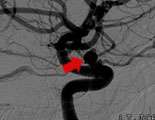

Fig. 2: a lateral view of the left internal carotid artery after coil embolization.

To treat the aneurysm, LaRue was admitted to the hospital the morning of the procedure, and under general anesthesia, the aneurysm was embolized with detachable coils (Fig.2).

The procedure was done through the artery at the top of LaRue's right leg. The only evidence of treatment is a small bandage over the groin area. LaRue stayed overnight and was discharged the next day. LaRue has had followup studies which showed her aneurysm remained occluded.